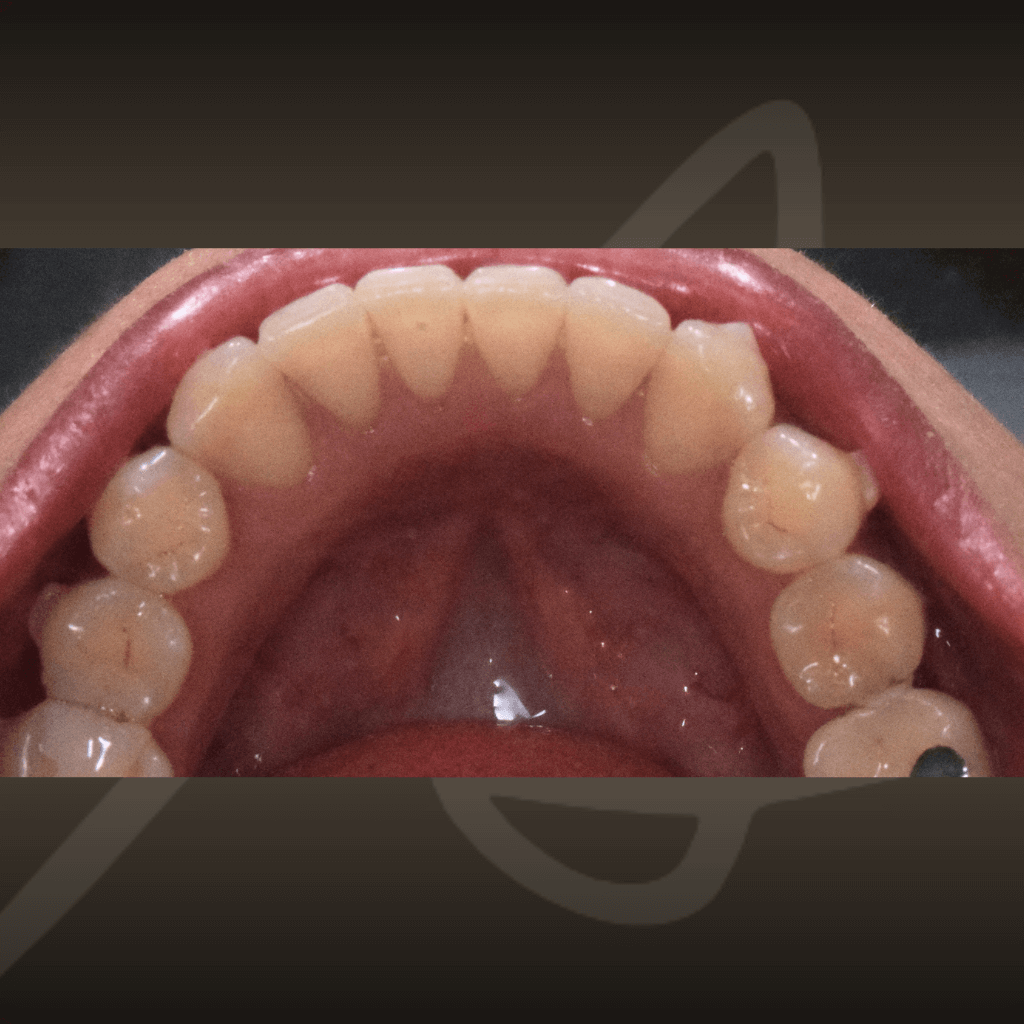

Ортодонтията не е само въпрос на подредба. Правилното лечение подобрява захапката, речта и създава стабилна основа за дългосрочно дентално здраве. Независимо от възрастта, ортодонтското лечение може да допринесе за по-добър функционален баланс и по-лесна поддръжка на зъбите във времето.